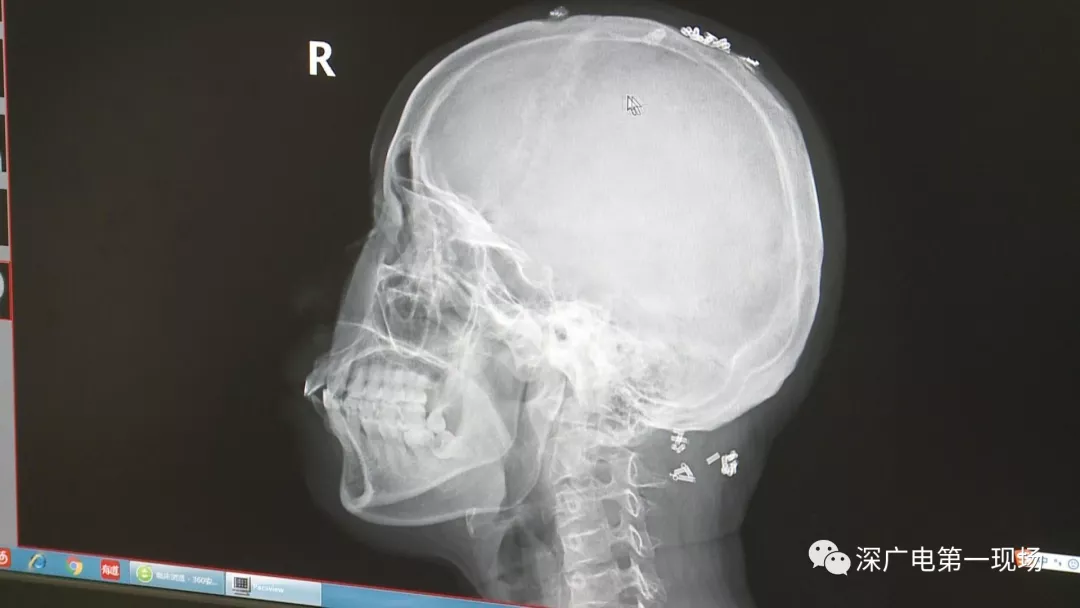

深圳一女子全身被植入彈簧圈,數(shù)量多到驚人!竟是為治這病…

據(jù)了解,這位患者周身的彈簧圈已經(jīng)固定了三年多,因?yàn)榛颊吒杏X(jué)治療效果不好,就來(lái)深圳求醫(yī)。